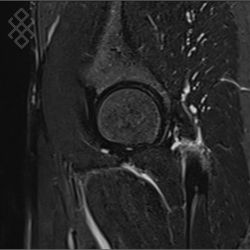

IRM du Bassin